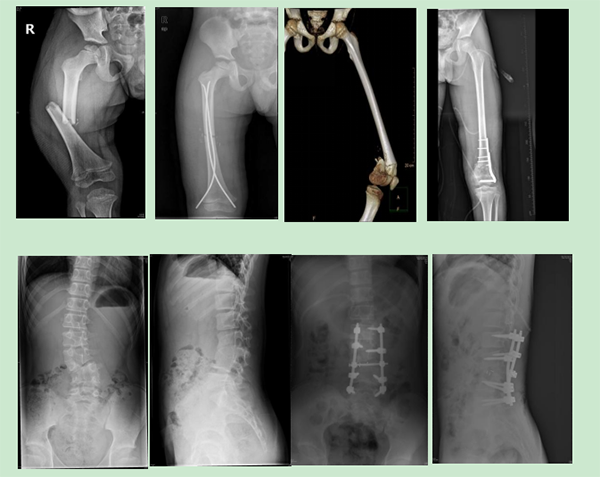

徐醫(yī)附院小兒骨科依托省級(jí)臨床重點(diǎn)?乒强破脚_(tái),擁有雄厚的醫(yī)療、科研實(shí)力,配備了脊柱手術(shù)顯微鏡、術(shù)中導(dǎo)航、脊柱微創(chuàng)內(nèi)鏡、關(guān)節(jié)鏡設(shè)備、術(shù)中神經(jīng)電生理監(jiān)測(cè)、超聲骨刀等先進(jìn)設(shè)備,極大地保證了患兒高難手術(shù)的精準(zhǔn)性和安全性。自2022年2月17日成立以來,徐醫(yī)附院小兒骨科秉承“微創(chuàng)化、精準(zhǔn)化”的治療原則,為淮海經(jīng)濟(jì)區(qū)兒童骨科患者提供優(yōu)質(zhì)的醫(yī)療服務(wù),贏得了廣泛贊譽(yù)。當(dāng)前,徐醫(yī)附院小兒骨科每月完成手術(shù)近40余臺(tái)。小兒肱骨髁上骨折、前臂骨折、股骨干骨折等常見骨折基本上都是經(jīng)皮微創(chuàng)完成,獲得患兒家長(zhǎng)的好評(píng)和信任。